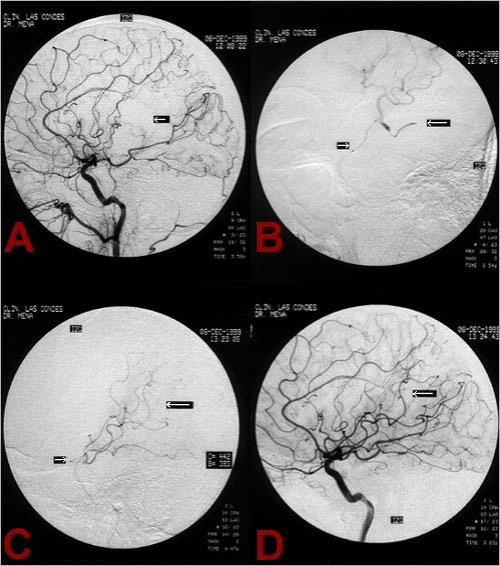

La paciente es una mujer de 69 años que consultó a la Clínica Las Condes por una afasia receptiva completa (afasia de Wernicke) de dos horas de evolución. La paciente tenía antecedentes de arritmia cardíaca (fibrilación auricular) pero no estaba recibiendo sus medicamentos de anticoagulación. De inmediato se efectuó una tomografía axial computada (TAC) cerebral, la que no mostró evidencias de hemorragia ni cambios precoces de infarto cerebral. En ese momento se decidió que la paciente era una buena candidata para trombolisis y se comenzó una infusión endovenosa de tPA (10% dosis según peso en bolo y 50% de dosis total en 45 minutos) con una dosis reducida de trombolisis EV. También se le inyectó el radiofármaco Tc99mHMPAO para posteriormente obtener un NeuroSPECT inicial. A continuación se efectúo una angiografía cerebral la que mostró una oclusión de la rama angular de la arteria cerebral media izquierda, probablemente de origen cardioembólico (Figura Ia). Se avanzó un microcatéter hasta la oclusión (Figura 1b) y se comenzó la trombolisis IA local, al mismo tiempo que se detuvo la infusión endovenosa de tPA después de haber recibido una dosis total de 24mg tPA EV. Al cabo de una hora, fue posible obtener una completa recanalización del vaso ocluido inyectando IA un total de 20 mg de tPA. Inmediatamente de haber recanalizado este vaso (Figura 1c y 1d), la paciente se recuperó de su afasia. El examen de NeuroSPECT pre-trombolisis demostró una zona de hipoperfusión profunda en el territorio de la arteria angular Figs. 2a y 2b.. La paciente ingresó a la Unidad CerebroVascular para un manejo médico especializado incluyendo manejo hemodinámico, anticoagulación después de las primeras 24 horas y manejo de su arritmia cardíaca. Un segundo NeuroSPECT de control a las 24 horas post-trombolisis, demostró una completa recuperación de la perfusión cerebral en el territorio de la arteria ocluida (Figura 2c y 2d). Por último, una resonancia magnética de cerebro (Figura 3) no reveló ninguna evidencia de infarto cerebral. La paciente fue dada de alta a los siete días sin ningún déficit neurológico.